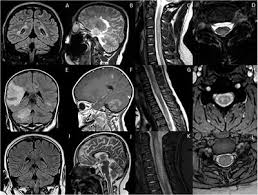

今回、上記3種類の遺伝子ワクチン接種後の代表的な脱髄疾患(多発性硬化症(MS: multiple sclerosis)、横断性脊髄炎(TM: transverse myelitis)、急性散在性[播種性]脳脊髄炎(acute disseminated encephalomyelitis (ADEM))、視神経脊髄炎スペクトラム障害(neuromyelitis optica spectrum disorder (NMOSD))、抗MOG(抗ミエリンオリゴデンドロサイト糖蛋白質)抗体関連疾患(myelin oligodendrocyte glycoprotein antibody disease (MOGAD)))の発症例を調べた研究が報告されています(A systematic review of cases of CNS demyelination following COVID-19 vaccination. J Neuroimmunol. 2022 Jan 15; 362: 577765)。